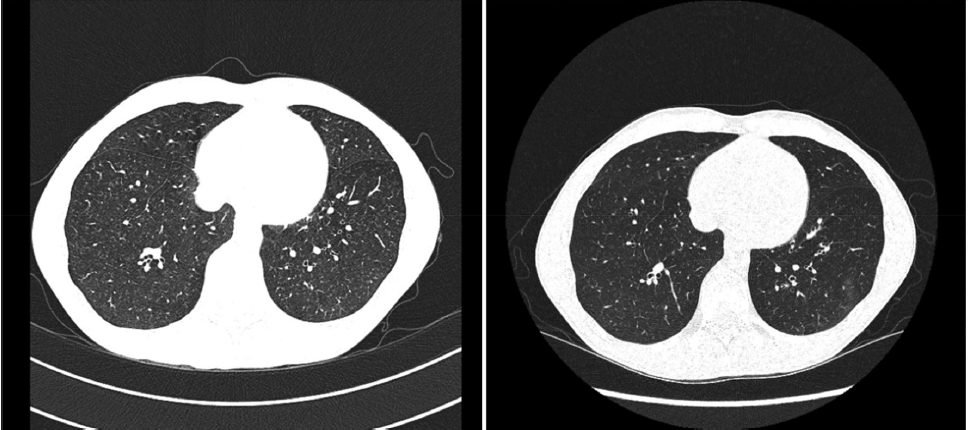

Pre-procedure images (left) demonstrate diffuse semi-solid centrilobular nodules that were present throughout both lungs. Post-procedure images (right) demonstrate significant clearing. Credit: D.C Chambers et al.

Australian scientists used a technique called whole lung lavage, which involves washing out the lungs, on six patients affected by artificial stone-associated silicosis, and say lung scans after the procedure suggested the technique may help those in the early stages of the disease. But further research is required to confirm whether this will translate into health benefits and improved survival. The disease has re-emerged in Australia and other wealthy countries because the tradies who make artificial stone benchtops can be exposed to high levels of silica dust that damages their lungs, and they are not always suitably protected from breathing the dust in. This form of silicosis is highly aggressive, and it develops faster and is more likely to kill patients than silicosis caused by mining, the experts say.